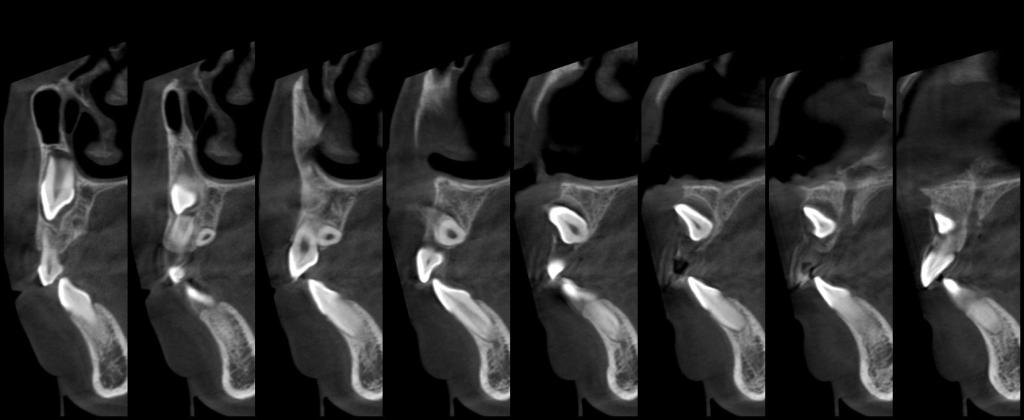

常规开展:数字化根尖片/横断牙合片、数字化口腔曲面体层片、头影测量侧位/正位片、手腕骨片、颅颌面CBCT、牙齿CBCT的检查以及涎腺造影、窦道 瘘管造影。

颅颌面CBCT

诊断范围涉及牙体牙髓病、牙周病、阻生牙/多生牙定位、种植牙术前CT评估分析、颞下颌关节CT诊断分析、,颌骨及涎腺疾病、颌面发育畸形、正畸治疗辅助诊断等大部分颌面部疾病,为临床医疗提供强有力的支持。